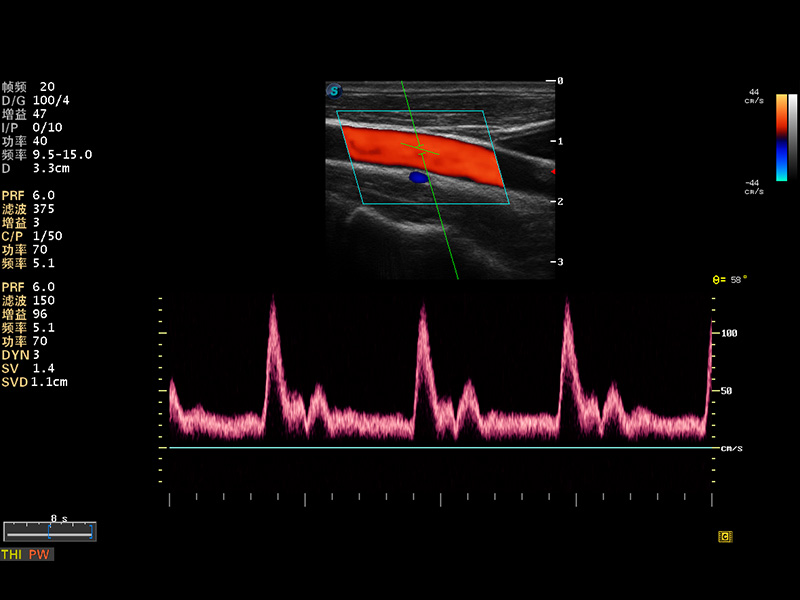

成像技术

多波束形成器

μ-Scan微米成像

谐波成像